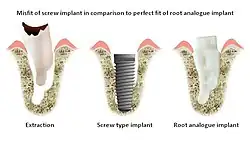

A root-analogue dental implant (RAI) – also known as a truly anatomic dental implant, or an anatomical/custom implant – is a medical device to replace one or more roots of a single tooth immediately after extraction.[1] In contrast to common titanium screw type implants, these implants are custom-made to exactly match the extraction socket of the specific patient. Thus there is usually no need for surgery.[2]

As technology has improved, so has implant success rate. Conventional titanium dental implants typically have success rates of 90–95% for 10-year follow-up periods, but this is based on questionable definitions of success.[5] The fundamental problem with conventional implant technology is that the patient must be altered to fit the screw or cylinder implant, rather than the other way around.

A tooth has one or more roots. Even a single-rooted tooth is nearly twice as wide in one direction as in the other. A cylindrical screw-type implant does not resemble a tooth, so invasive surgery is needed to make it fit into an existing tooth socket. Such surgery involves drilling into healthy bone, filling gaps between implant and bone either with bone or bone substitutes, and frequently sinus lift procedures.

RAIs are custom made to perfectly fit the tooth socket of a specific patient immediately after tooth extraction. Therefore every implant is unique. As an optimised root-form it is much more than a simple 1:1 replica of a tooth. Since it exactly fills the gap left after the tooth is extracted, surgery is rarely needed. The implant can be produced from a copy of the extracted tooth, an impression of the tooth socket, or from a CT scan or CBCT scan.[7] The advantage of a CBCT scan is that the implant can be produced before extraction. With the former methods, it takes one or two days to fabricate an implant.

- Natural form: a custom milled anatomic implant replicates the natural form of a tooth, so it simply fits into the tooth socket. Like the original tooth, a root analogue implant can have single- and multi-rooted forms.